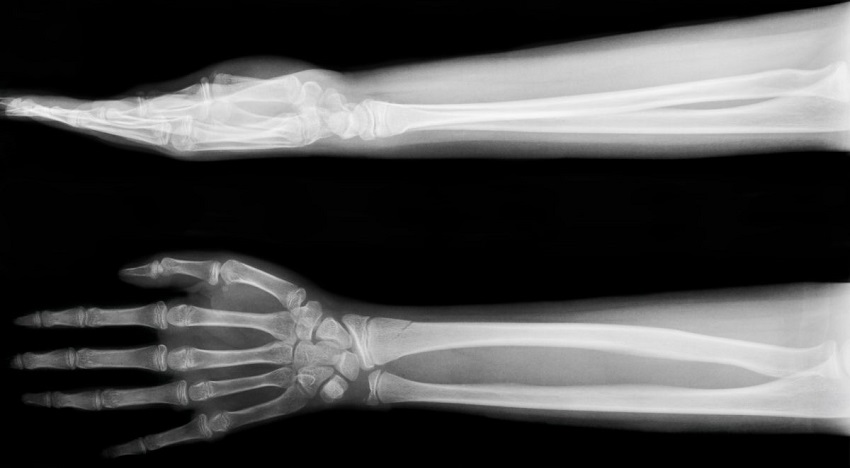

Рентгенография кистей (со снимком)

Рентгенологическое исследование кистей рук является неинвазивным методом исследования внутренней структуры костных тканей.

Что показывает рентген кисти?

• Различные изменения в мышцах, сухожилиях и лимфатических узлах.

• Воспалительный процесс.

• Вывихи.

• Трещины, микротрещины и истончение костей.

• Общее состояние всех отделов кисти: фаланг пальцев, запястье и пясть.